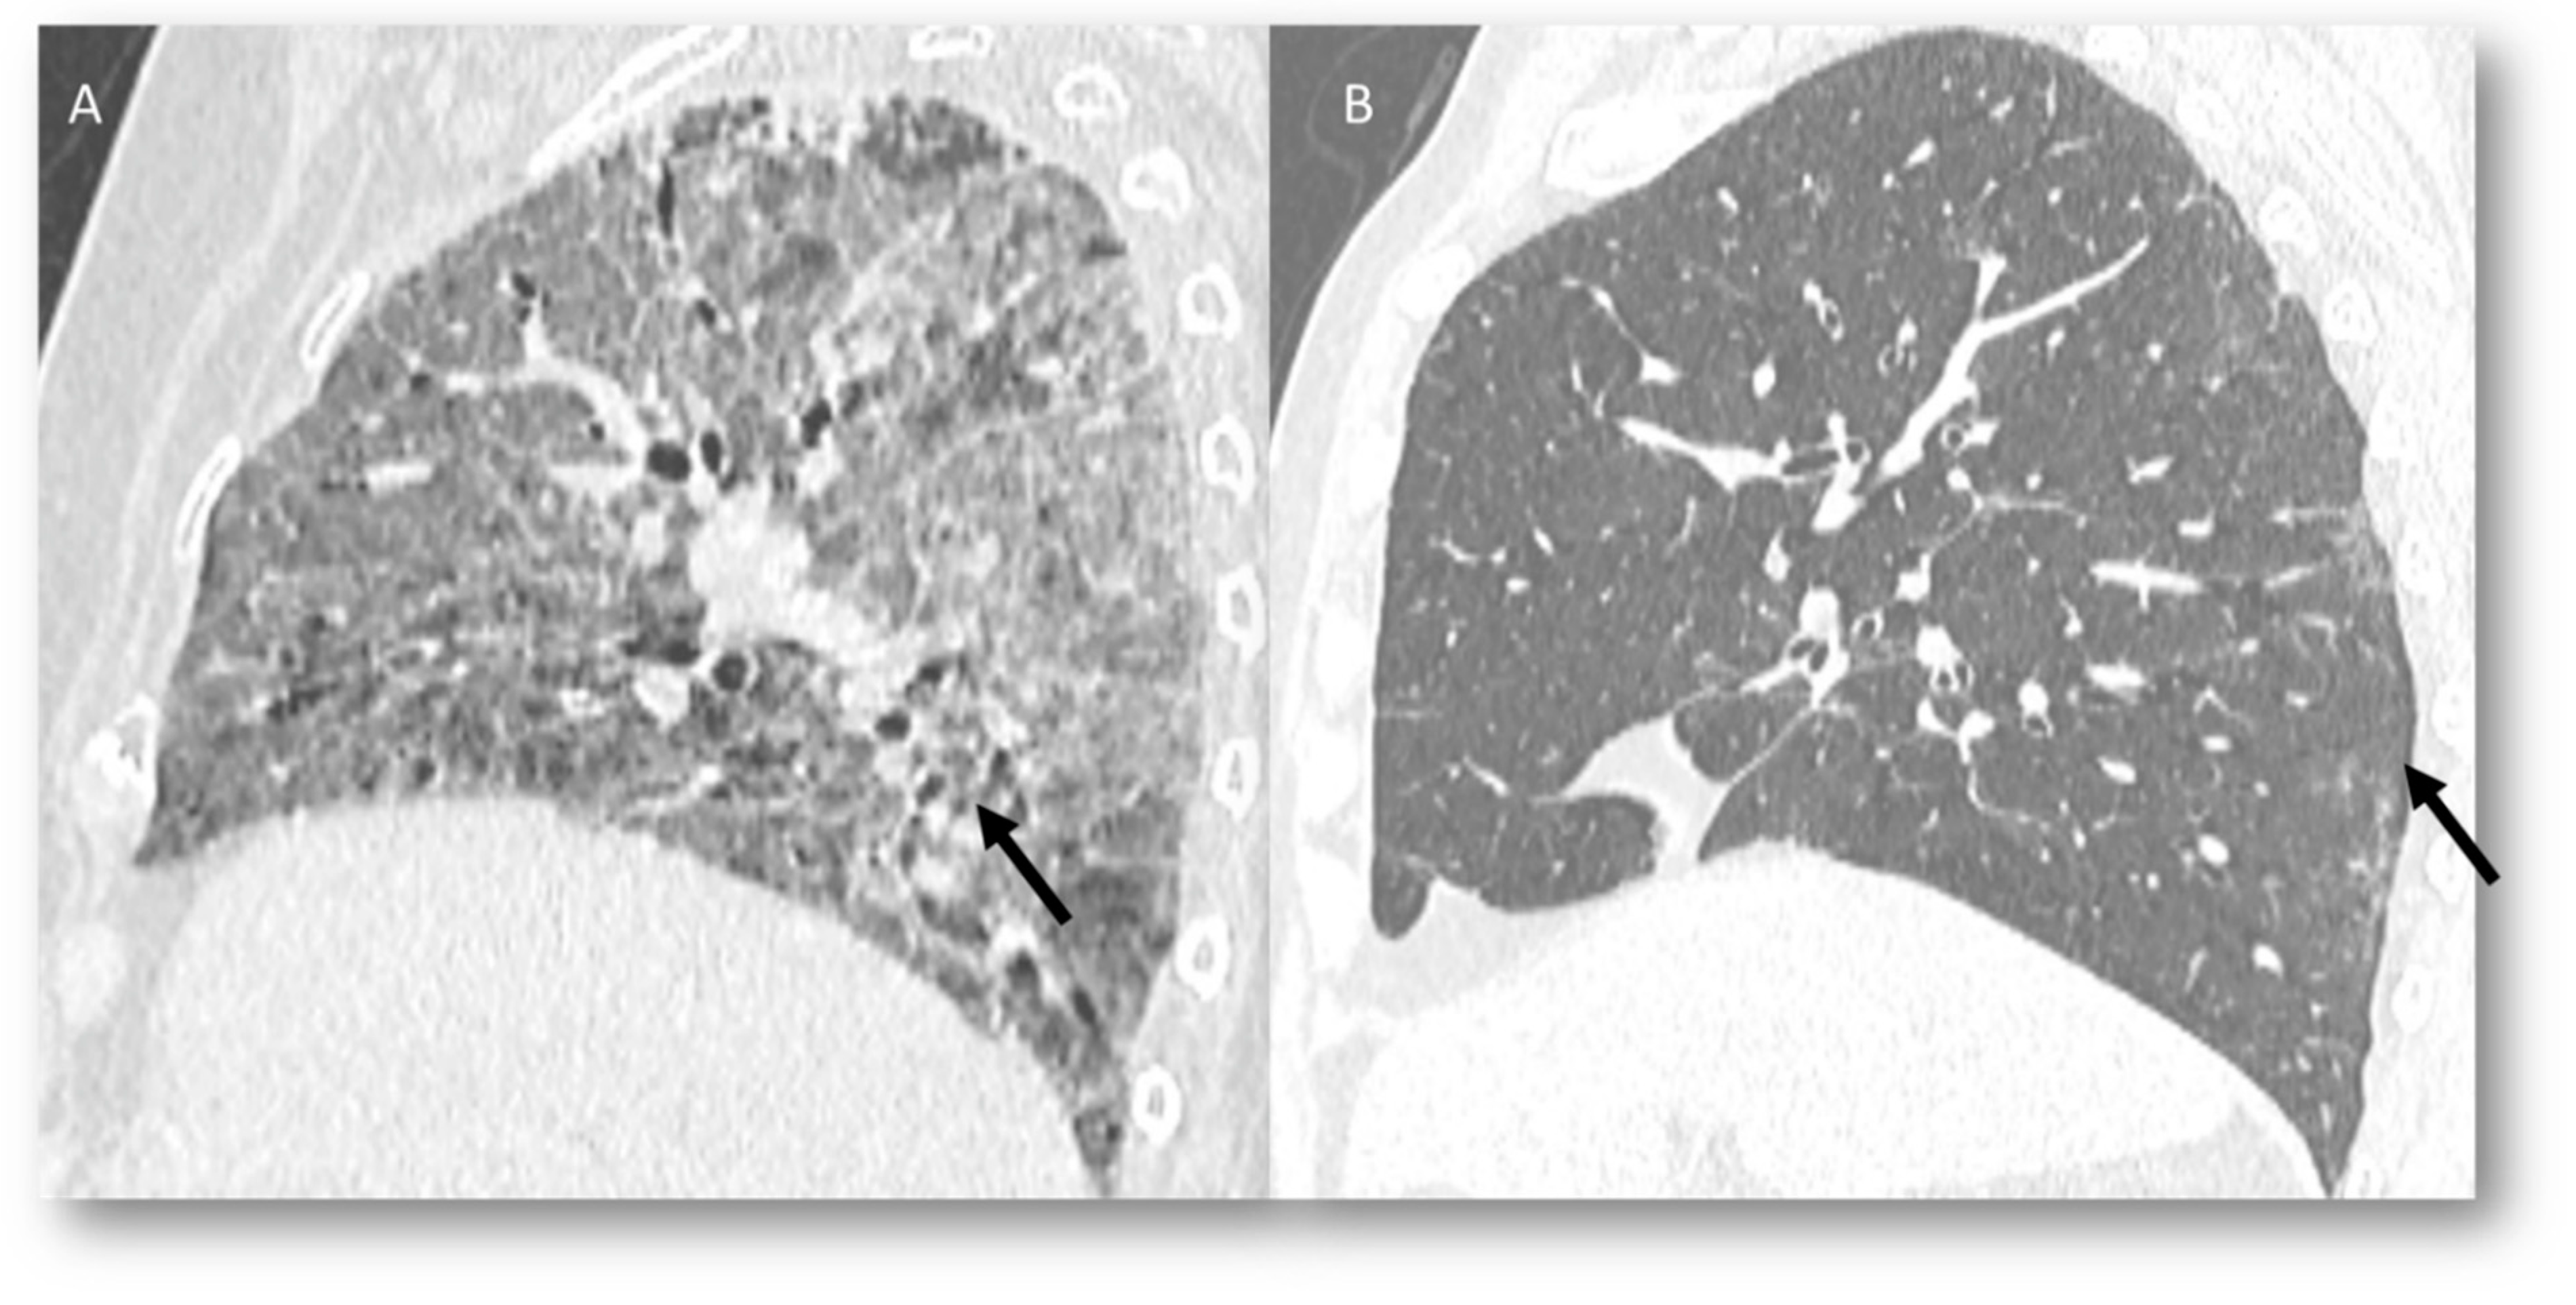

3.2. Immune-Related Pneumonia

3.5. Progression Disease: Pulmonary Lymphangitis Carcinomatosa

3.6. Machine Learning